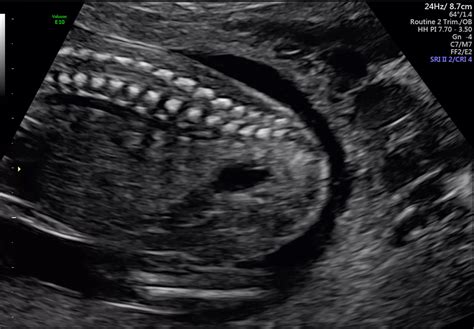

The 20 week pregnancy sonography is a detailed ultrasound examination that focuses on evaluating the baby's anatomy. This scan is more thorough than the earlier ultrasounds and is designed to check for any structural abnormalities. The ultrasound technician will examine various parts of the baby's body, including the brain, heart, spine, kidneys, and limbs, to ensure everything is developing normally.

During the 20 week pregnancy sonography, the technician will look for various developmental milestones. Some of the key findings include:

• Heartbeat: A strong and regular heartbeat is a positive sign of the baby's health.

• Brain Development: The brain structures, including the ventricles and cerebellum, are assessed for normal development.

• Spine and Limbs: The spine is checked for any abnormalities, and the limbs are examined for proper length and movement.

• Kidneys and Bladder: The kidneys and bladder are evaluated to ensure they are functioning correctly.

• Amniotic Fluid: The amount of amniotic fluid is measured to ensure it is within the normal range.